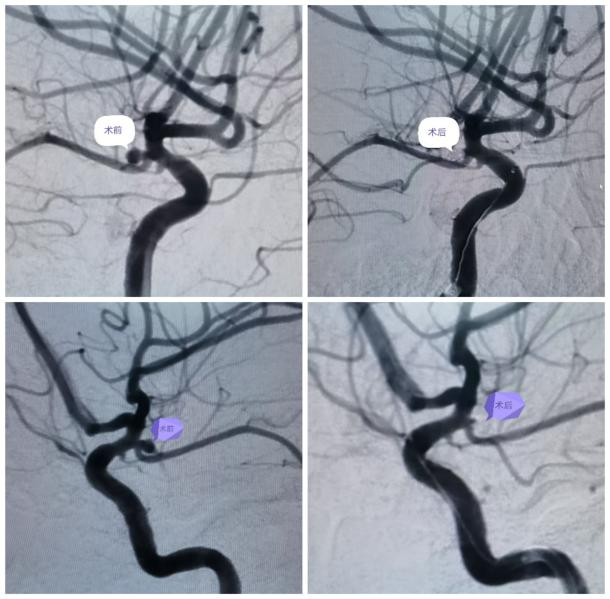

最近,患者苏女士突发意识不清,伴右侧肢体偏瘫,肌力1级,来我院急诊医学科就诊,头部CT提示蛛网膜下腔出血,Hunt-Hess(分级)3级。经神经外科荆泽林主治医师会诊后立即收住入院同时向科主任王伟志汇报患者病情,科室集体讨论后考虑颅内动脉瘤破裂致蛛网膜下腔出血,急行脑血管造影术。

术中证实术前判断正确,科主任王伟志、主任医师云亚滨、副主任医师陈波考虑左侧后交通动脉瘤破裂致蛛网膜下腔出血,征得家属同意,进一步行颅内动脉瘤栓塞术。

术前

术后